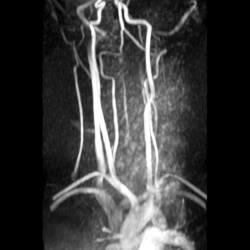

Сосуды шеи